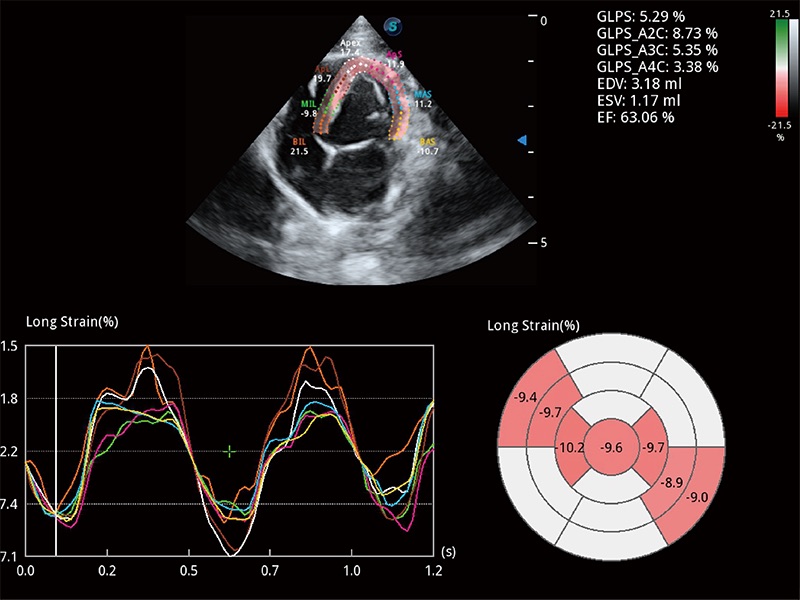

通過心肌識別技術(shù)與二維斑點追蹤技術(shù)相結(jié)合,對心臟的超聲圖像進行量化分析。計算心肌17個節(jié)段的應變、應變率、速度、位移等,并通過牛眼圖的形式進行呈現(xiàn)。